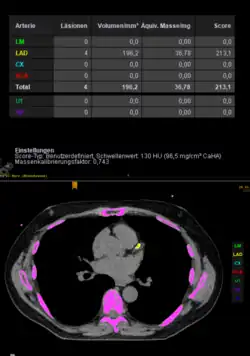

Kalkscore

Zunächst werden Aufnahmen mit geringer Strahlendosis und ohne Kontrastmittelgabe durchgeführt. Die Koronarkalkmenge wird für jedes Gefäß einzeln und insgesamt quantitativ gemessen. Der Agatston-Score wird aus Dichte und Volumen der Kalkplaques berechnet und aufaddiert. Ein Score von >400 gilt als unabhängiger Risikofaktor für eine KHK;[9] man spricht hier von einem Schwellenphänomen.[10]